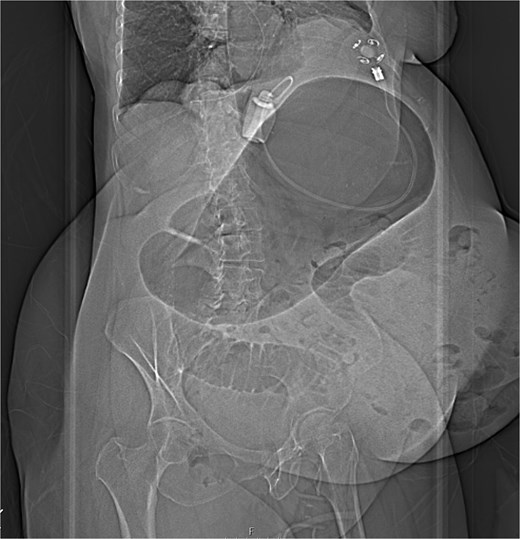

The CT also showed a large ventral hernia in the anterior abdominal wall on the left side, with several entrances and exits for intestinal loops within the hernia. The proximal loops appeared dilated up to 5 cm, with fat stranding and slight fluid between the loops, as well as mild prominence of the mesenteric blood vessels. Distal loops were collapsed, raising suspicion of high-grade obstruction with ischemic bowel involvement (Fig. 5).

CT axial view—obstructed ventral hernia with proximal small bowel loop dilatation.